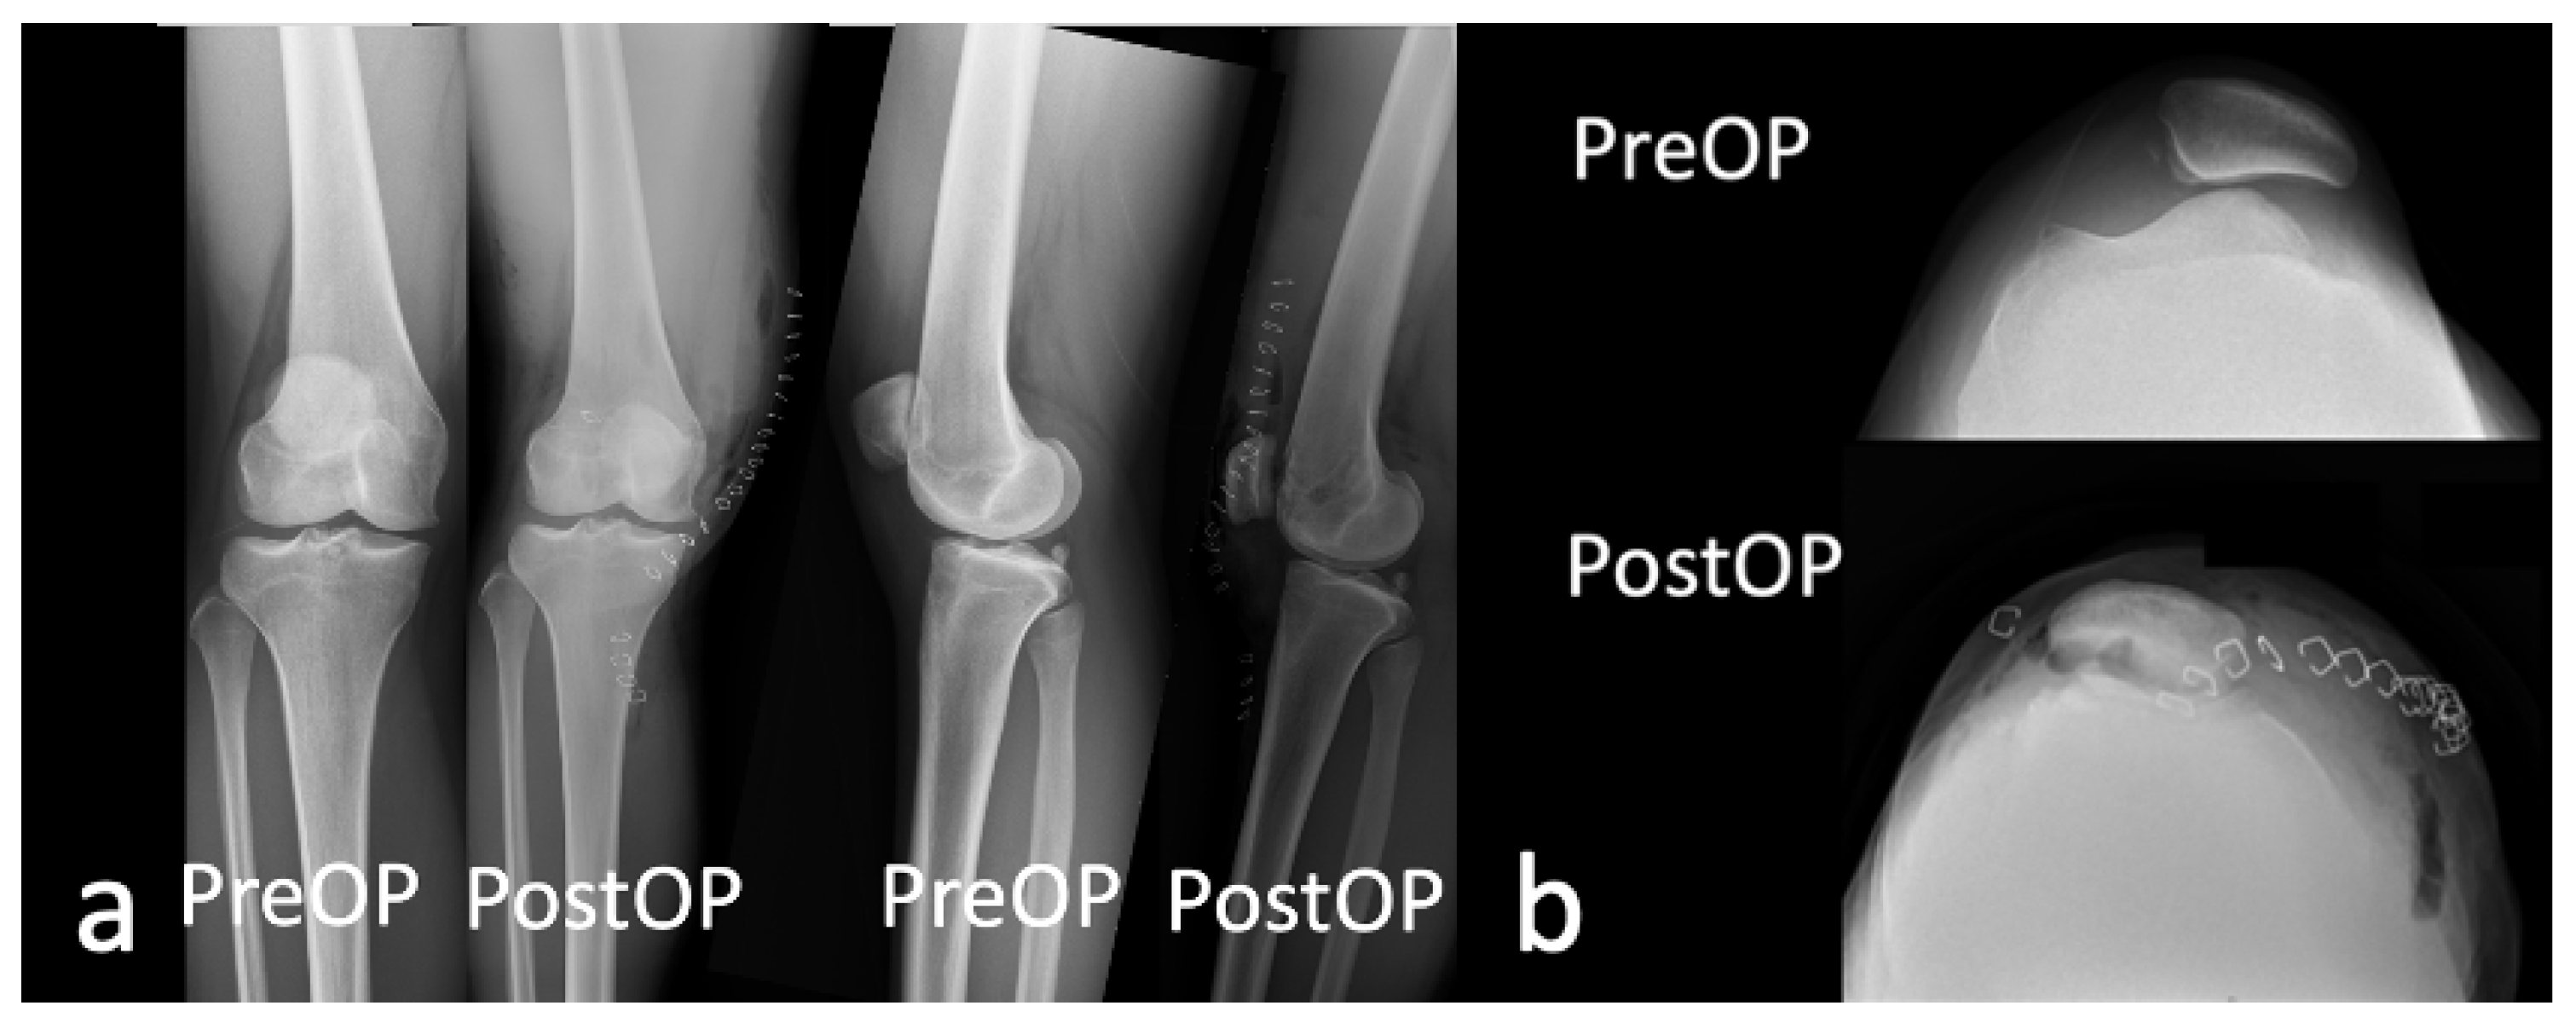

2.1. Case

2.2. Surgical Procedure

4. Conclusions